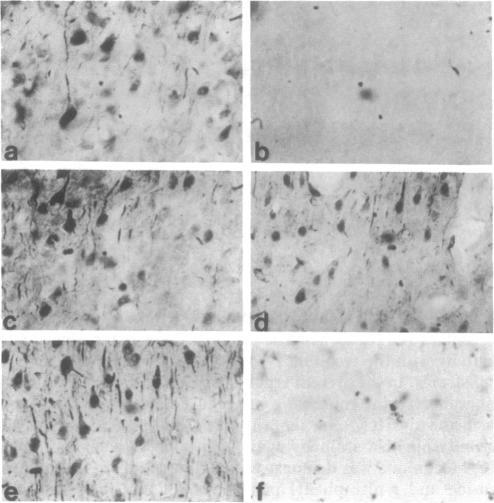

Cellular regulation by certain growth factor receptors and protooncogene products involves tyrosine kinase activity with the resultant tyrosine phosphorylation of protein substrates. In the present report we describe the distribution of phosphotyrosine-containing material detected by immunocytochemistry (ICC) in the rat forebrain. Specificity of the affinity-purified antibody against phosphotyrosine used in the ICC technique was demonstrated by the ability of phosphotyrosine and p-nitrophenyl phosphate but not phosphoserine, phosphothreonine, or L-tyrosine to inhibit the immunostaining reaction. With ICC, relatively high amounts of phosphotyrosine-positive material were observed in neurons in specific structures that included the supraoptic, paraventricular, and arcuate nuclei; the median eminence; medial habenula; subfornical organ; and piriform cortex. Moderate to high amounts were present in the cerebral cortical layers II-IV and in the pyramidal cell layer of the hippocampus. Small to moderate amounts were detected in a few other locations. Glial elements showed minimal staining. Other areas of the rat forebrain failed to react with this antibody. Importantly, the distribution of the areas positive for phosphotyrosine agreed to a remarkable extent with the distribution of the brain insulin receptor, which itself has tyrosine kinase activity. These findings suggest a relationship between the insulin receptor and the increased phosphotyrosine content of these neurons and support the concept that the brain insulin receptor is active in vivo.

某些生长因子受体和原癌基因产物对细胞的调节涉及酪氨酸激酶活性,其结果是蛋白质底物发生酪氨酸磷酸化。在本报告中,我们描述了通过免疫细胞化学(ICC)检测到的含磷酸酪氨酸物质在大鼠前脑的分布情况。ICC技术中使用的抗磷酸酪氨酸亲和纯化抗体的特异性通过以下能力得以证明:磷酸酪氨酸和对硝基苯磷酸能够抑制免疫染色反应,而磷酸丝氨酸、磷酸苏氨酸或L-酪氨酸则不能。通过ICC观察到,在特定结构的神经元中存在相对大量的磷酸酪氨酸阳性物质,这些结构包括视上核、室旁核和弓状核;正中隆起;内侧缰核;穹窿下器官;以及梨状皮质。在大脑皮质的II-IV层和海马的锥体细胞层中存在中等至大量的该物质。在其他一些位置检测到少量至中等量的该物质。神经胶质成分显示出极少的染色。大鼠前脑的其他区域与该抗体无反应。重要的是,磷酸酪氨酸阳性区域的分布在很大程度上与脑胰岛素受体的分布一致,而脑胰岛素受体本身具有酪氨酸激酶活性。这些发现表明胰岛素受体与这些神经元中磷酸酪氨酸含量的增加之间存在关联,并支持脑胰岛素受体在体内具有活性这一概念。